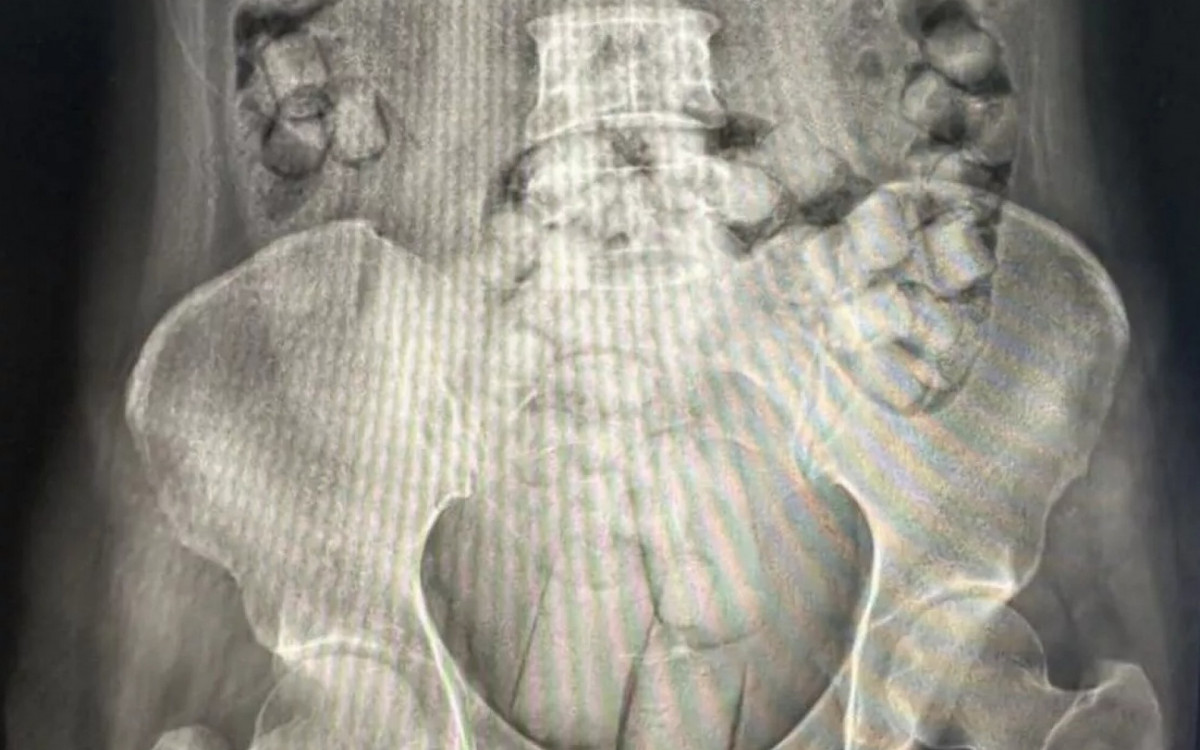

Imagem de raio-X mostra as cápsulas de heroína no corpo de uma das acusadasDivulgação/Polícia de Taiwan

De acordo com a Agência Central de Notícias de Taiwan (CNA), agentes do controle antidrogas identificaram indícios do crime durante a fiscalização de rotina, em um desembarque de um voo proveniente da Tailândia. Após a revista e exames de raios-X, as mulheres foram levadas ao hospital, onde os médicos retiraram todas as embalagens de droga com segurança. Mais de 100 cápsulas estavam escondidas no ânus das acusadas. As embalagens maiores foram engolidas.